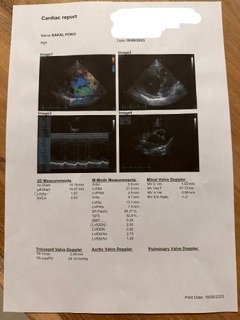

最新のデータです🫀

ぽこの最新のデータです🫀

ぽこは、心臓が今年の4月頃から大きくなって来ました。

その際に、ドクターから大きくなり始めてから統計上半年で肺水腫になるといわれ、その際に20%の子が命を落としますと言われました。。。

手術をしないと、10月頃には命を落とす可能性が20%もあると言うことになります。。。😔

心臓がパンパンで、今は沢山のことを我慢させてしまっています😔